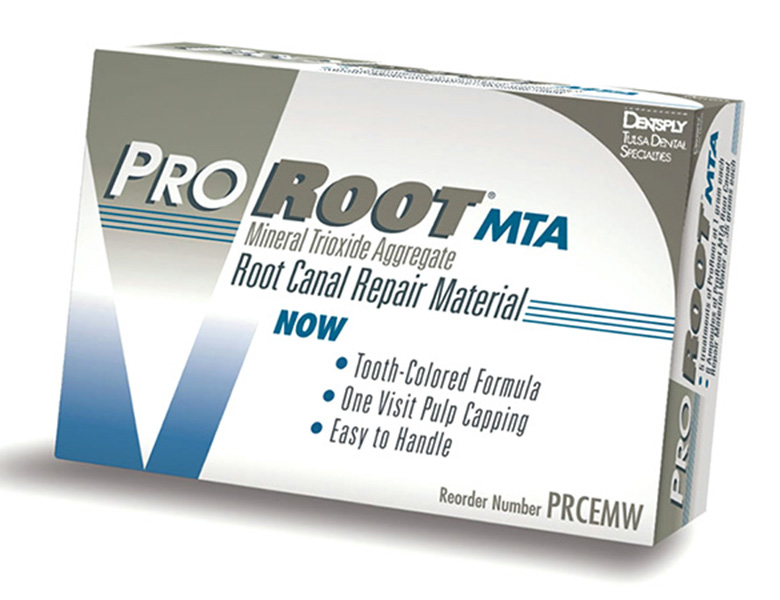

MTAセメント:歯の「最後の砦」を守る薬剤

根の先に穴が開いてしまっている場合や、非常に深いむし歯で神経の一部を守りたい場合など、通常の薬剤では対応できないケースがあります。

そのような際、当院では高い殺菌性と組織再生を促す「MTAセメント」を使用します。

これにより、以前なら抜歯していたような症例でも、歯を残せる確率が格段に上がりました。